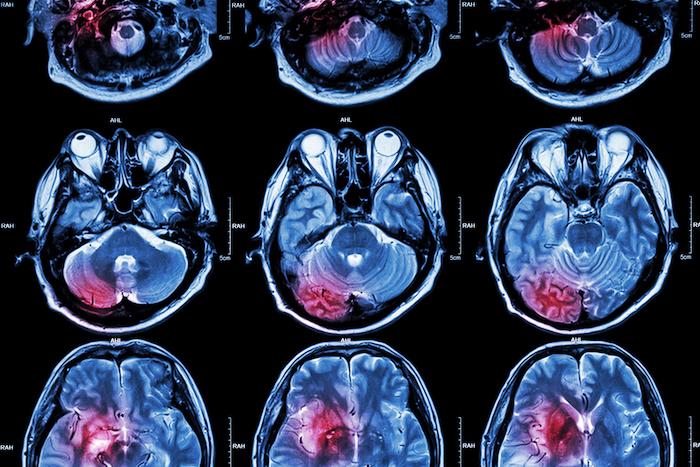

Après un AVC, il y a fréquemment une atteinte chronique du bras et de la main. Des chercheurs rapportent dans une récente étude que la stimulation du nerf vague - associée à un entraînement de rééducation -améliore la récupération de cette fonction motrice. Leurs résultats ont été publiés dans la revue Stroke.

Actuellement, les options thérapeutiques permettant de restaurer la fonction du bras et de la main chez les personnes victimes d’AVC sont limitées. Or la perte de la capacité de supination (mouvement de rotation externe de la main et de l’avant-bras) contribue à l’invalidité post-AVC.